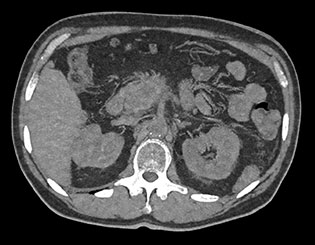

Выполните просмотр требуемой области с помощью нескольких решений благодаря эксклюзивному приложению Spectral Magic Glass для вычленения данных о составе тканей.

Здесь представлена серия изображений, на которых значения воксела обозначают эффективное атомное число. Эффективное атомное число может быть дробным, обозначающим какой-либо элемент, соединение или смесь. Данное число может отличаться от порядкового номера, указанного в периодической таблице. Единица для обозначения — Z.